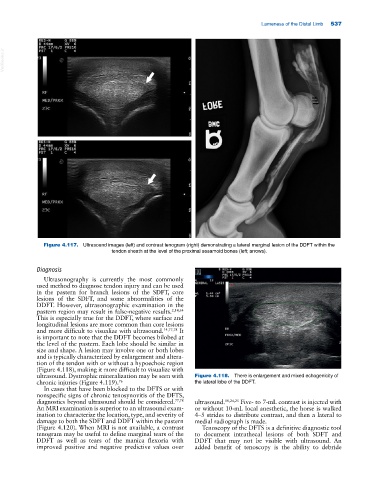

Figure 4.117. Ultrasound images (left) and contrast tenogram (right) demonstrating a lateral marginal lesion of the DDFT within the

tendon sheath at the level of the proximal sesamoid bones (left; arrows).